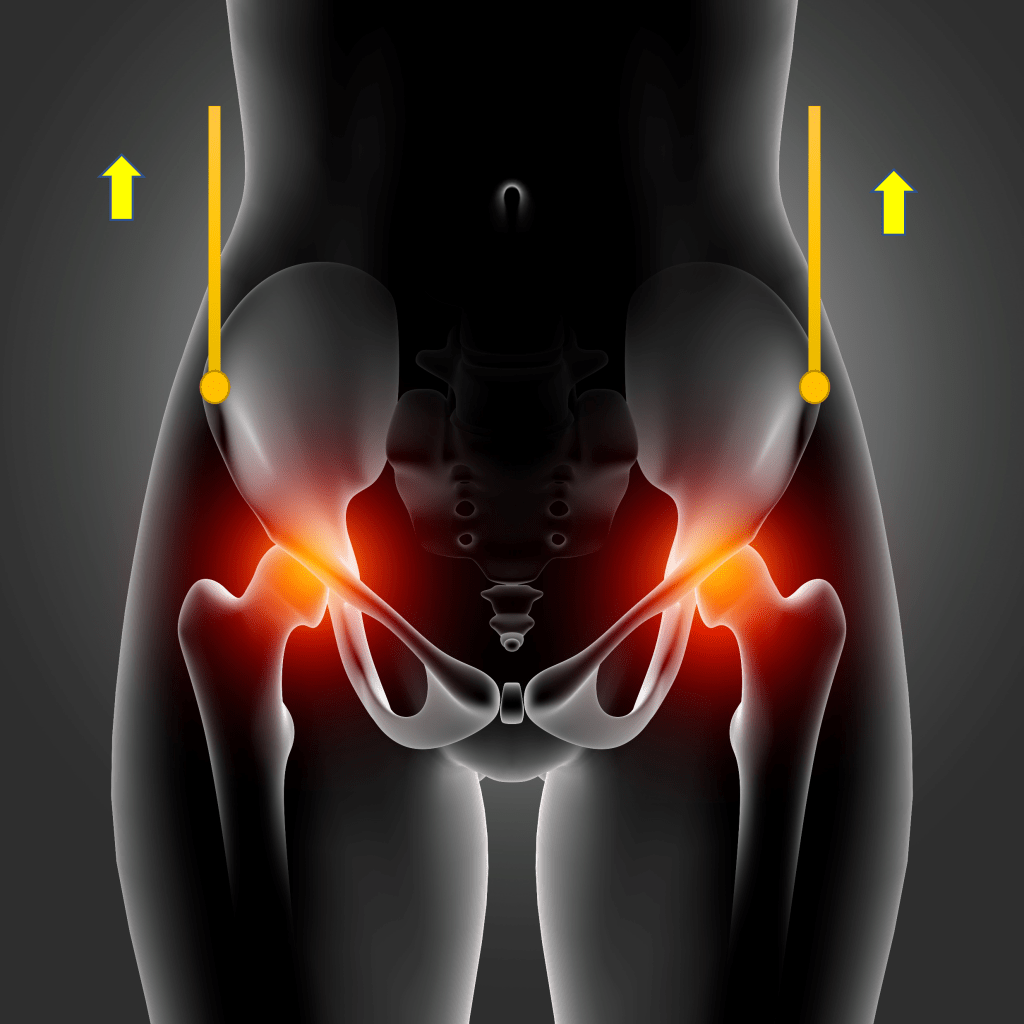

✔Quando estiver em pé ou caminhando, tente manter o quadril encaixado e o abdome contraído. Os músculos do abdome, bem como os músculos das costas são responsáveis pela sustentação do tronco. Se o abdome estiver fraco, a “barriguinha vai cair” pendendo essa parte do corpo para frente. Isso acontece mesmo que você seja “do tipo esbelta“. Se faltar força nesses músculos, as costas serão sobrecarregadas causando a dor. Um truque para encaixar o quadril é fazer o seguinte: posicione-se em pé de frente ao espelho e imagine duas linhas; grude uma extremidade de cada linha em cada ossinho do quadril (logo abaixo da cintura); segure a extremidade solta de cada linha imaginária (uma em cada mão) e puxe para cima, de modo a tracionar a pelve levemente para frente e para cima (mantendo os pés firmes no chão).

No início, a gente esquece de manter a posição, mas depois de várias repetições, nos acostumamos com a postura correta. Veja a ilustração abaixo👇